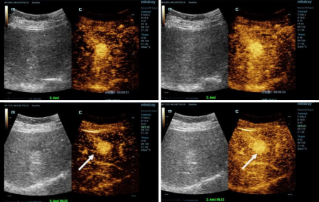

![More Precise Diagnoses with HiFR CEUS]() More Precise Diagnoses with HiFR CEUSContrast-enhanced ultrasound (CEUS) is a very dynamic field and in the past few years technological innovations have further increased image quality. One of these innovations is high frame-rate contrast-enhanced ultrasound (HiFR CEUS) which can generate up to ten times more images than conventional ultrasound ŌĆō in the same time.Ultrasound | General imaging 2022-12-16

More Precise Diagnoses with HiFR CEUSContrast-enhanced ultrasound (CEUS) is a very dynamic field and in the past few years technological innovations have further increased image quality. One of these innovations is high frame-rate contrast-enhanced ultrasound (HiFR CEUS) which can generate up to ten times more images than conventional ultrasound ŌĆō in the same time.Ultrasound | General imaging 2022-12-16 -